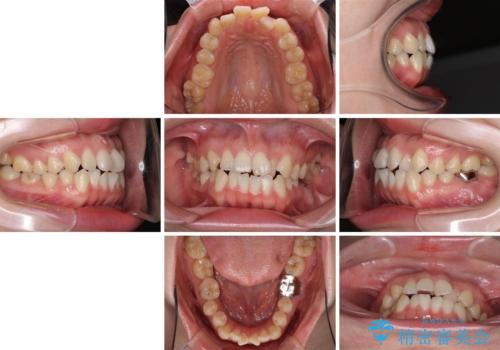

- 前歯のデコボコが気になるとのことで来院された患者様です。

奥の銀歯も気になっていたため、矯正治療後にセラミッククラウンにて補綴することとしました。

1年半程度の期間を見込んでいましたが、上下の真ん中の位置をできる限り合わせるための調整に少し時間がかかってしまいました。

咬み合わせが安定し、前歯の汚れも付きにくくなりました。